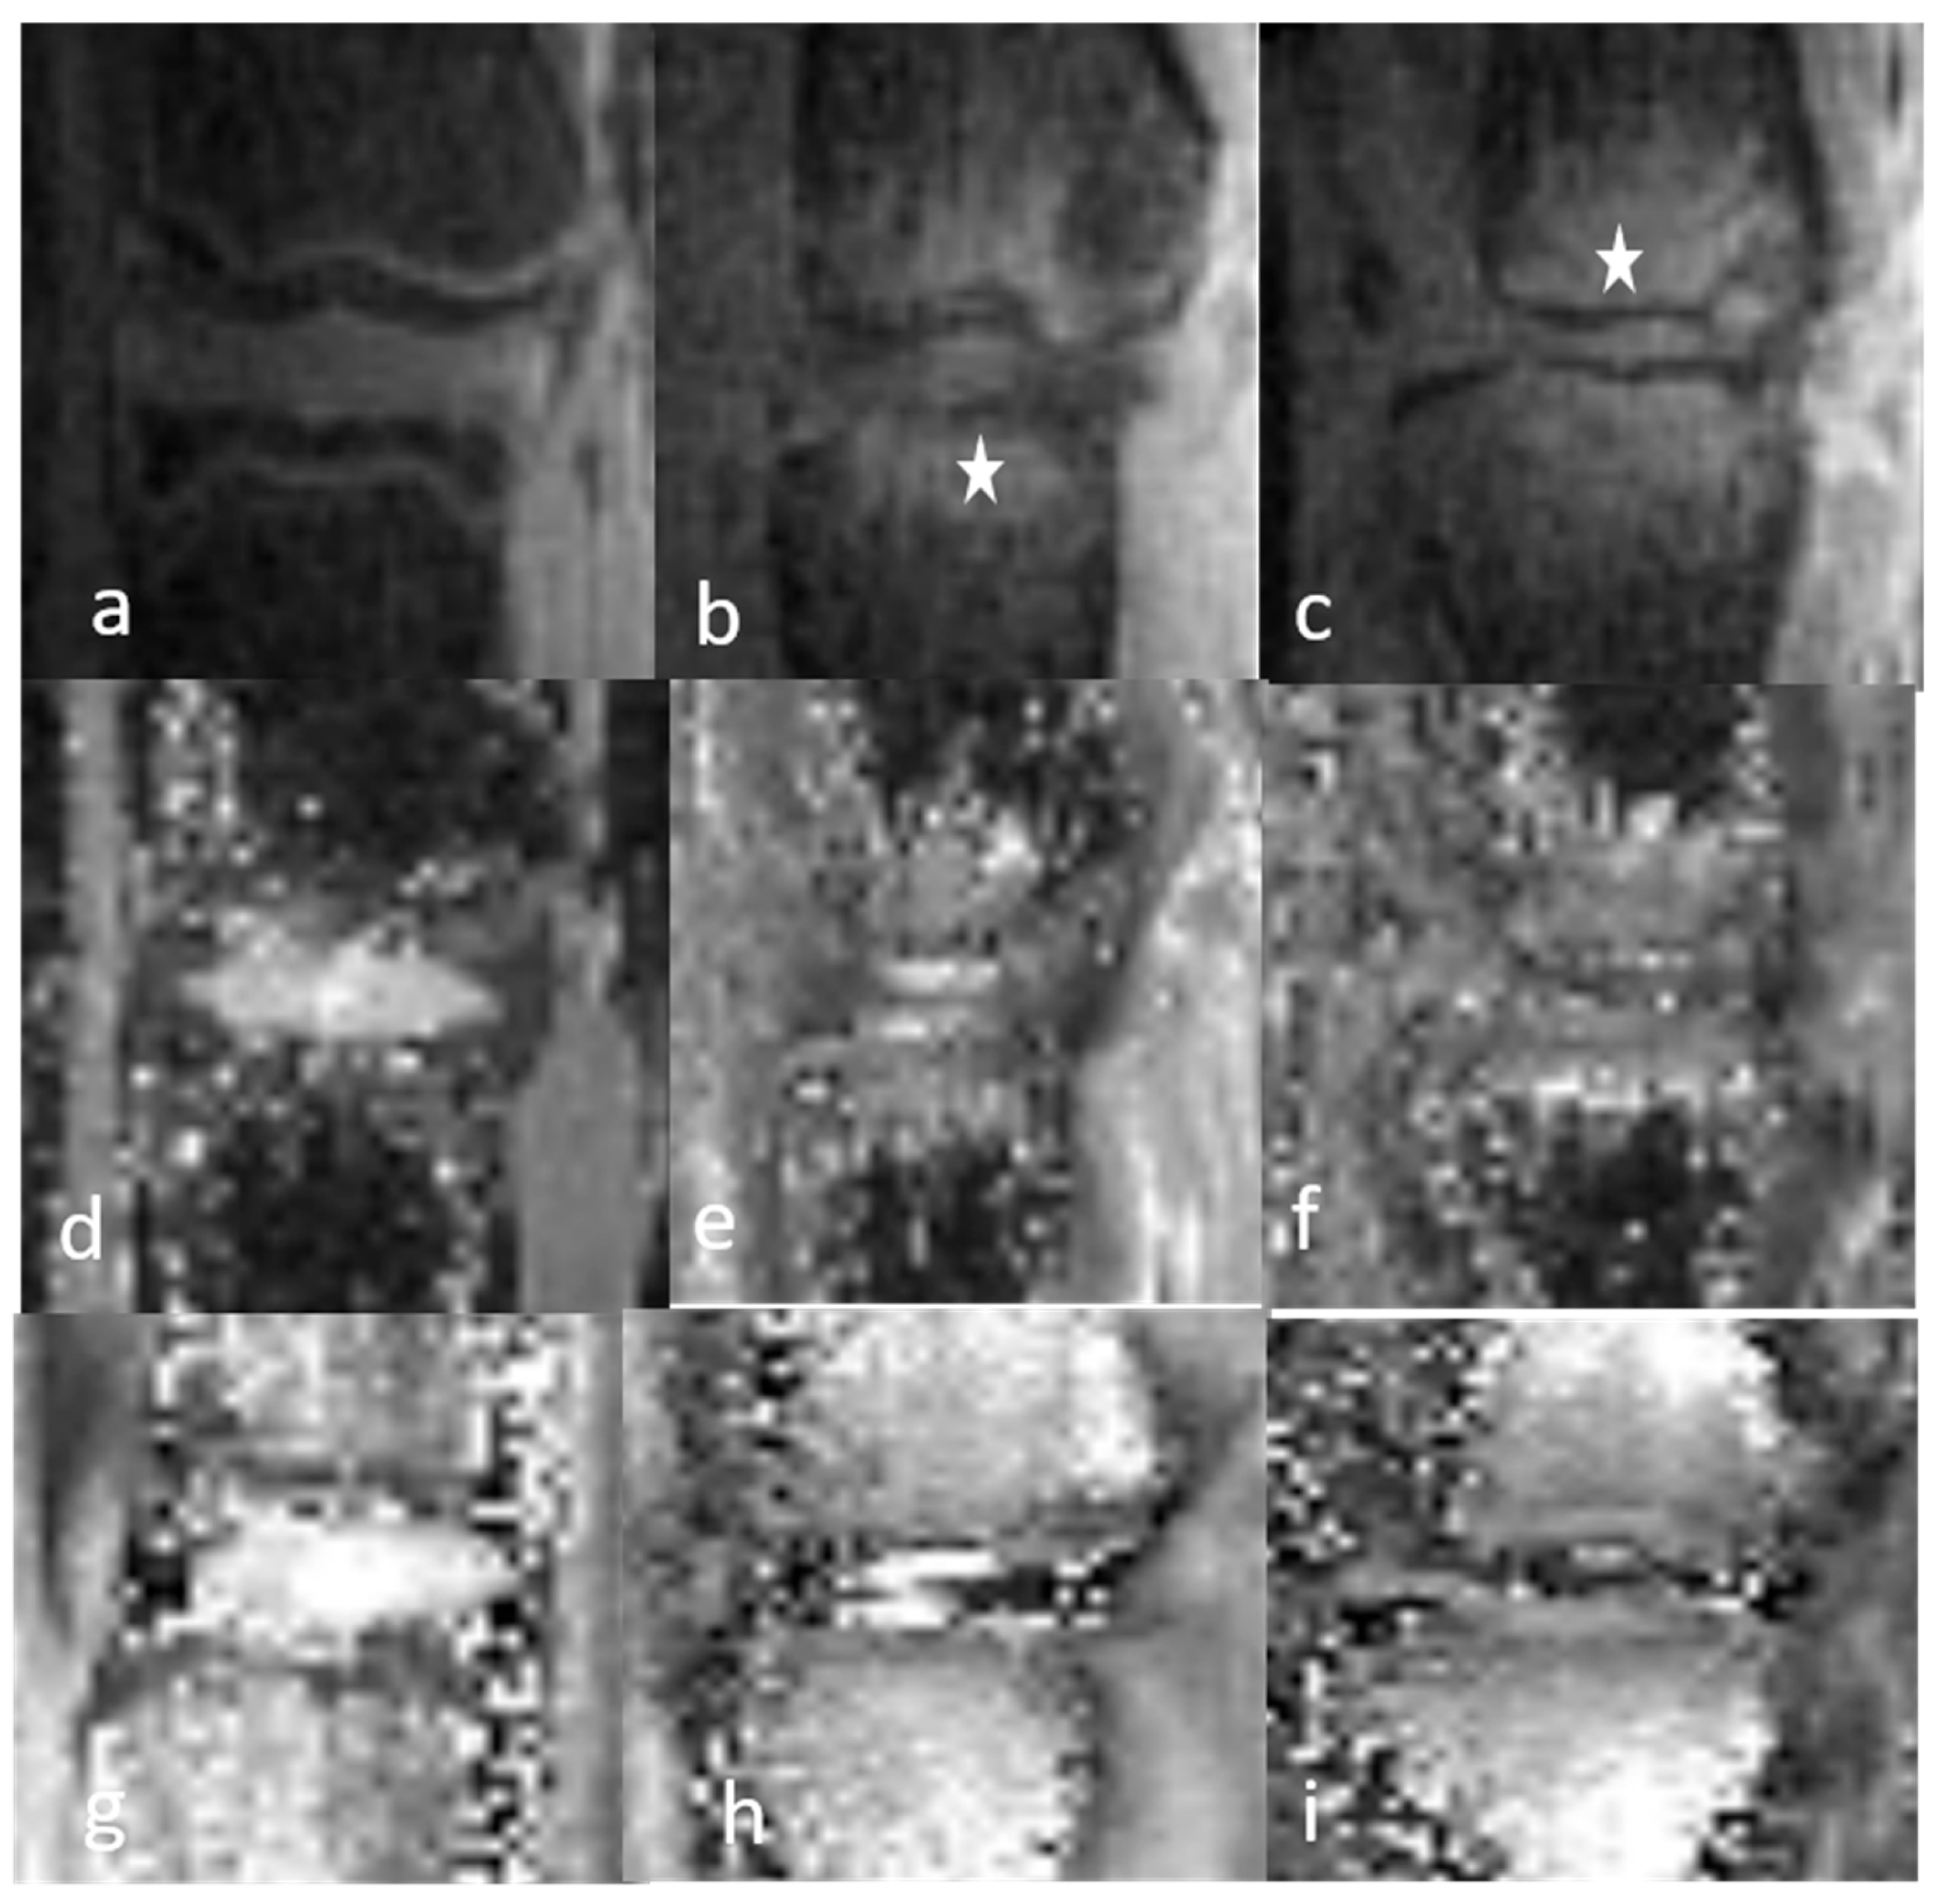

3.1.1. Qualitative Analysis of the Normal DVC (Table 1 and Table 2)

3.1.2. Qualitative Analysis of the DVC in DDD Rats (Table 3)